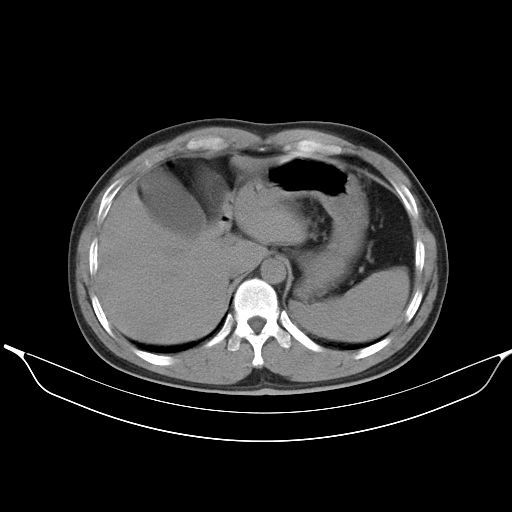

标题: CT25490:男,40岁,体检发现;无其它不适。 [打印本页]

标题: CT25490:男,40岁,体检发现;无其它不适。

2、轻度脂肪肝。

1、均为转移,原发灶不在肺内。2、肺癌肺转移。